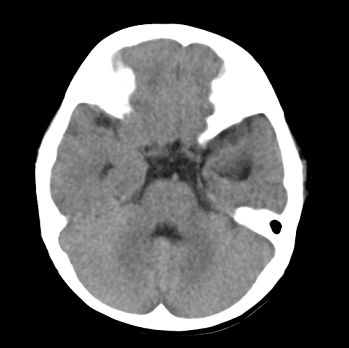

以下是引用22222222在2008-6-9 21:03:00的发言:[br]病灶周围见脑组织包绕,上部可见等或稍高密度壁环绕,壁且见小点钙化-----考虑皮样囊肿或表皮样囊肿可能,但侧脑室颞角内病灶不排除.